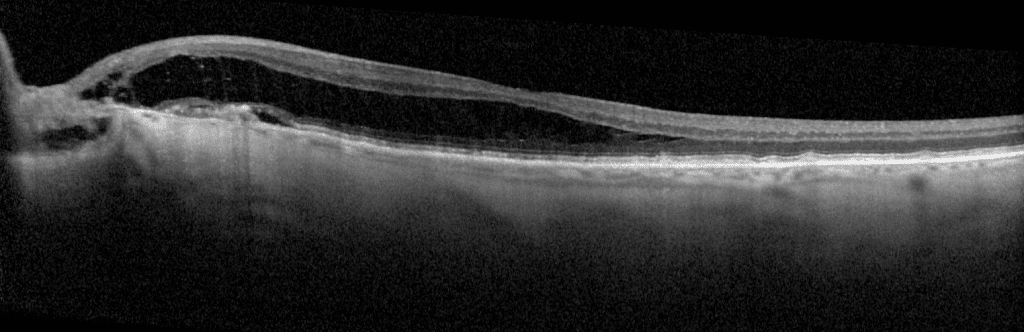

Due to their proximity, this fluid affects the local juxtapapillary retina and may extend to the macula, often leading to serous detachments or schisis-like IRF in the macula (Figure 1).1 The fluid within the retina typically communicates directly with the optic disc’s anomalous cavitation. In contrast, any subretinal fluid usually does not, but instead, seeps into the subretinal space via a subclinical microbreak in the outer retina.1 Recall that serous fluid looks optically empty on optical coherence tomography (OCT), which is the case in the fluid seen here.

Figure 1. Optic disc pit with retinoschisis-like IRF extending into the macula, communicating directly with the disc’s anomalous cavitation. This patient also developed juxtapapillary CNV with juxtapapillary subretinal fluid surrounding early subretinal fibrosis.